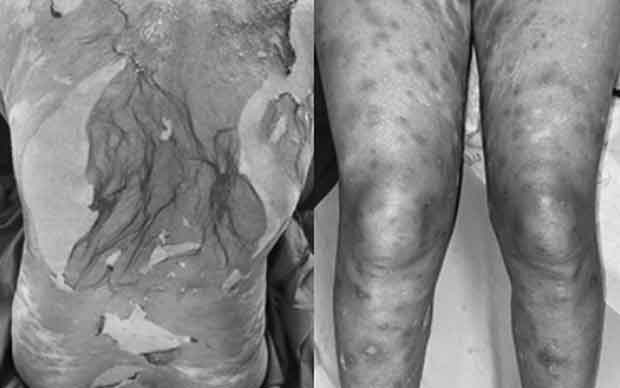

Bệnh diễn biến 7 ngày trước khi vào viện. Ban đầu, bệnh nhân xuất hiện dát đỏ thẫm, sưng nề vùng môi, sau đó các dát đỏ lan nhanh ra tay, chân, thân mình, hình thành thêm mụn nước, bọng nước, có sốt cao.

Khám lúc vào viện thấy dát đỏ thẫm, liên kết với nhau thành mảng, bọng nước, hoại tử da lan tỏa. Các niêm mạc không có thương tổn. Các xét nghiệm của bệnh nhân có hạ bạch cầu và tăng men gan.

Bệnh nhân được chẩn đoán hoại tử thượng bì nhiễm độc (hội chứng Lyell) và điều trị tích cực tại khoa, dùng các thuốc đặc hiệu (corticoid toàn thân) kèm chăm sóc hỗ trợ. Sau 7 ngày điều trị, thương tổn da khô, bắt đầu tái tạo thượng bì, không có bọng nước mới.